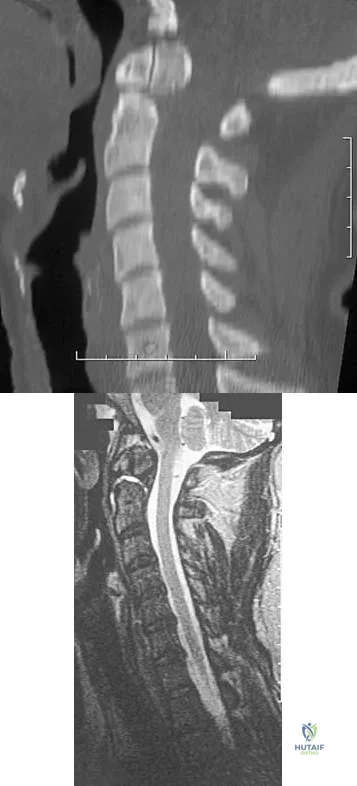

A 42-year-old woman reports that she has low back pain and had a transient loss of consciousness after falling off a horse. She denies having neck pain but notes that she was involved in a motor vehicle accident 2 years ago and had neck pain at that time. Examination reveals full range of motion of the neck and no localized tenderness. The neurologic examination is normal. A lateral radiograph of the cervical spine is obtained. Figures 41a and 41b show CT and MRI scans. What is the most likely diagnosis?